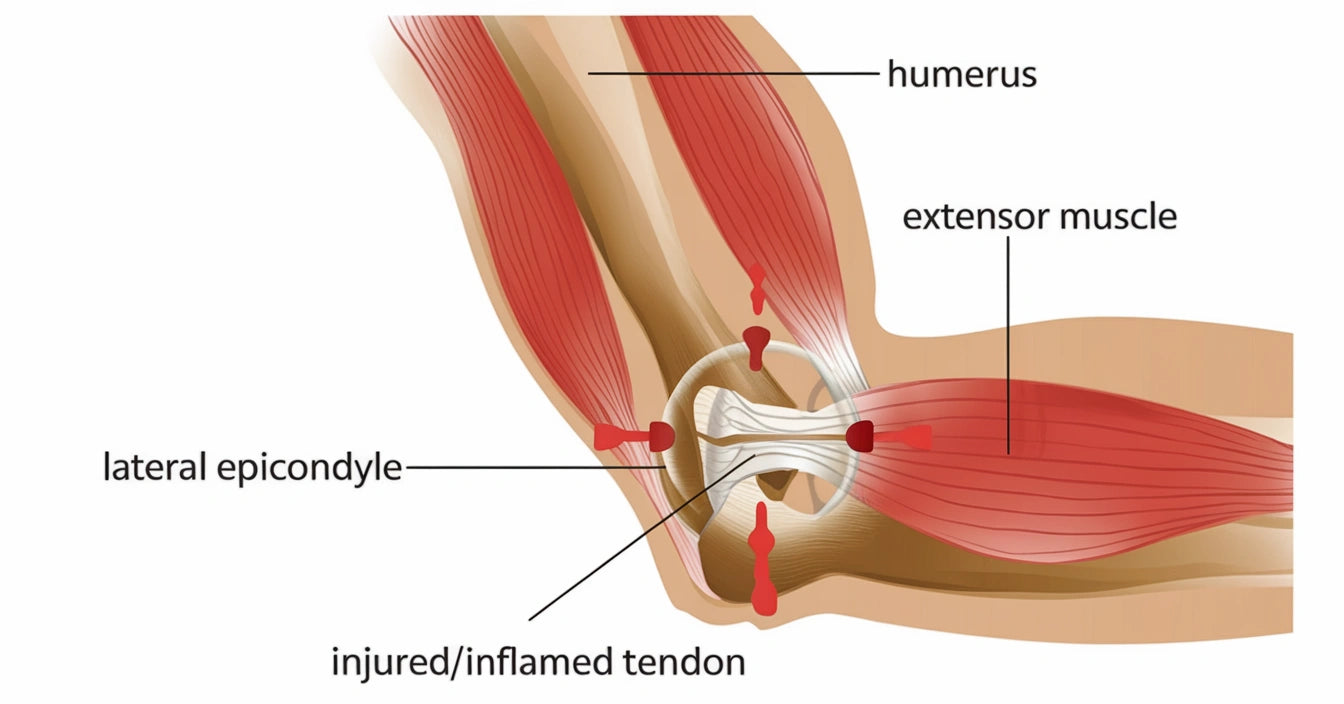

Armbågssmärta kan komma smygande eller plötsligt – särskilt vid upprepade rörelser eller belastning. Tennisarmbåge, musarm och inflammation är vanliga orsaker. I våra guider får du veta mer om diagnos och behandling.